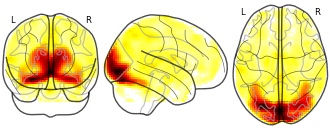

"name": "Multi_VBMsmaller_fMRIenhanced",

"description": "Multi-modal analysis in BPD. Brain regions exhibiting smaller gray matter and enhanced activation during emotion processing in BPD compared to healthy controls. Note: Results were thresholded at p<.0025. Note2: Results were updated (see Erratum for this publication).",